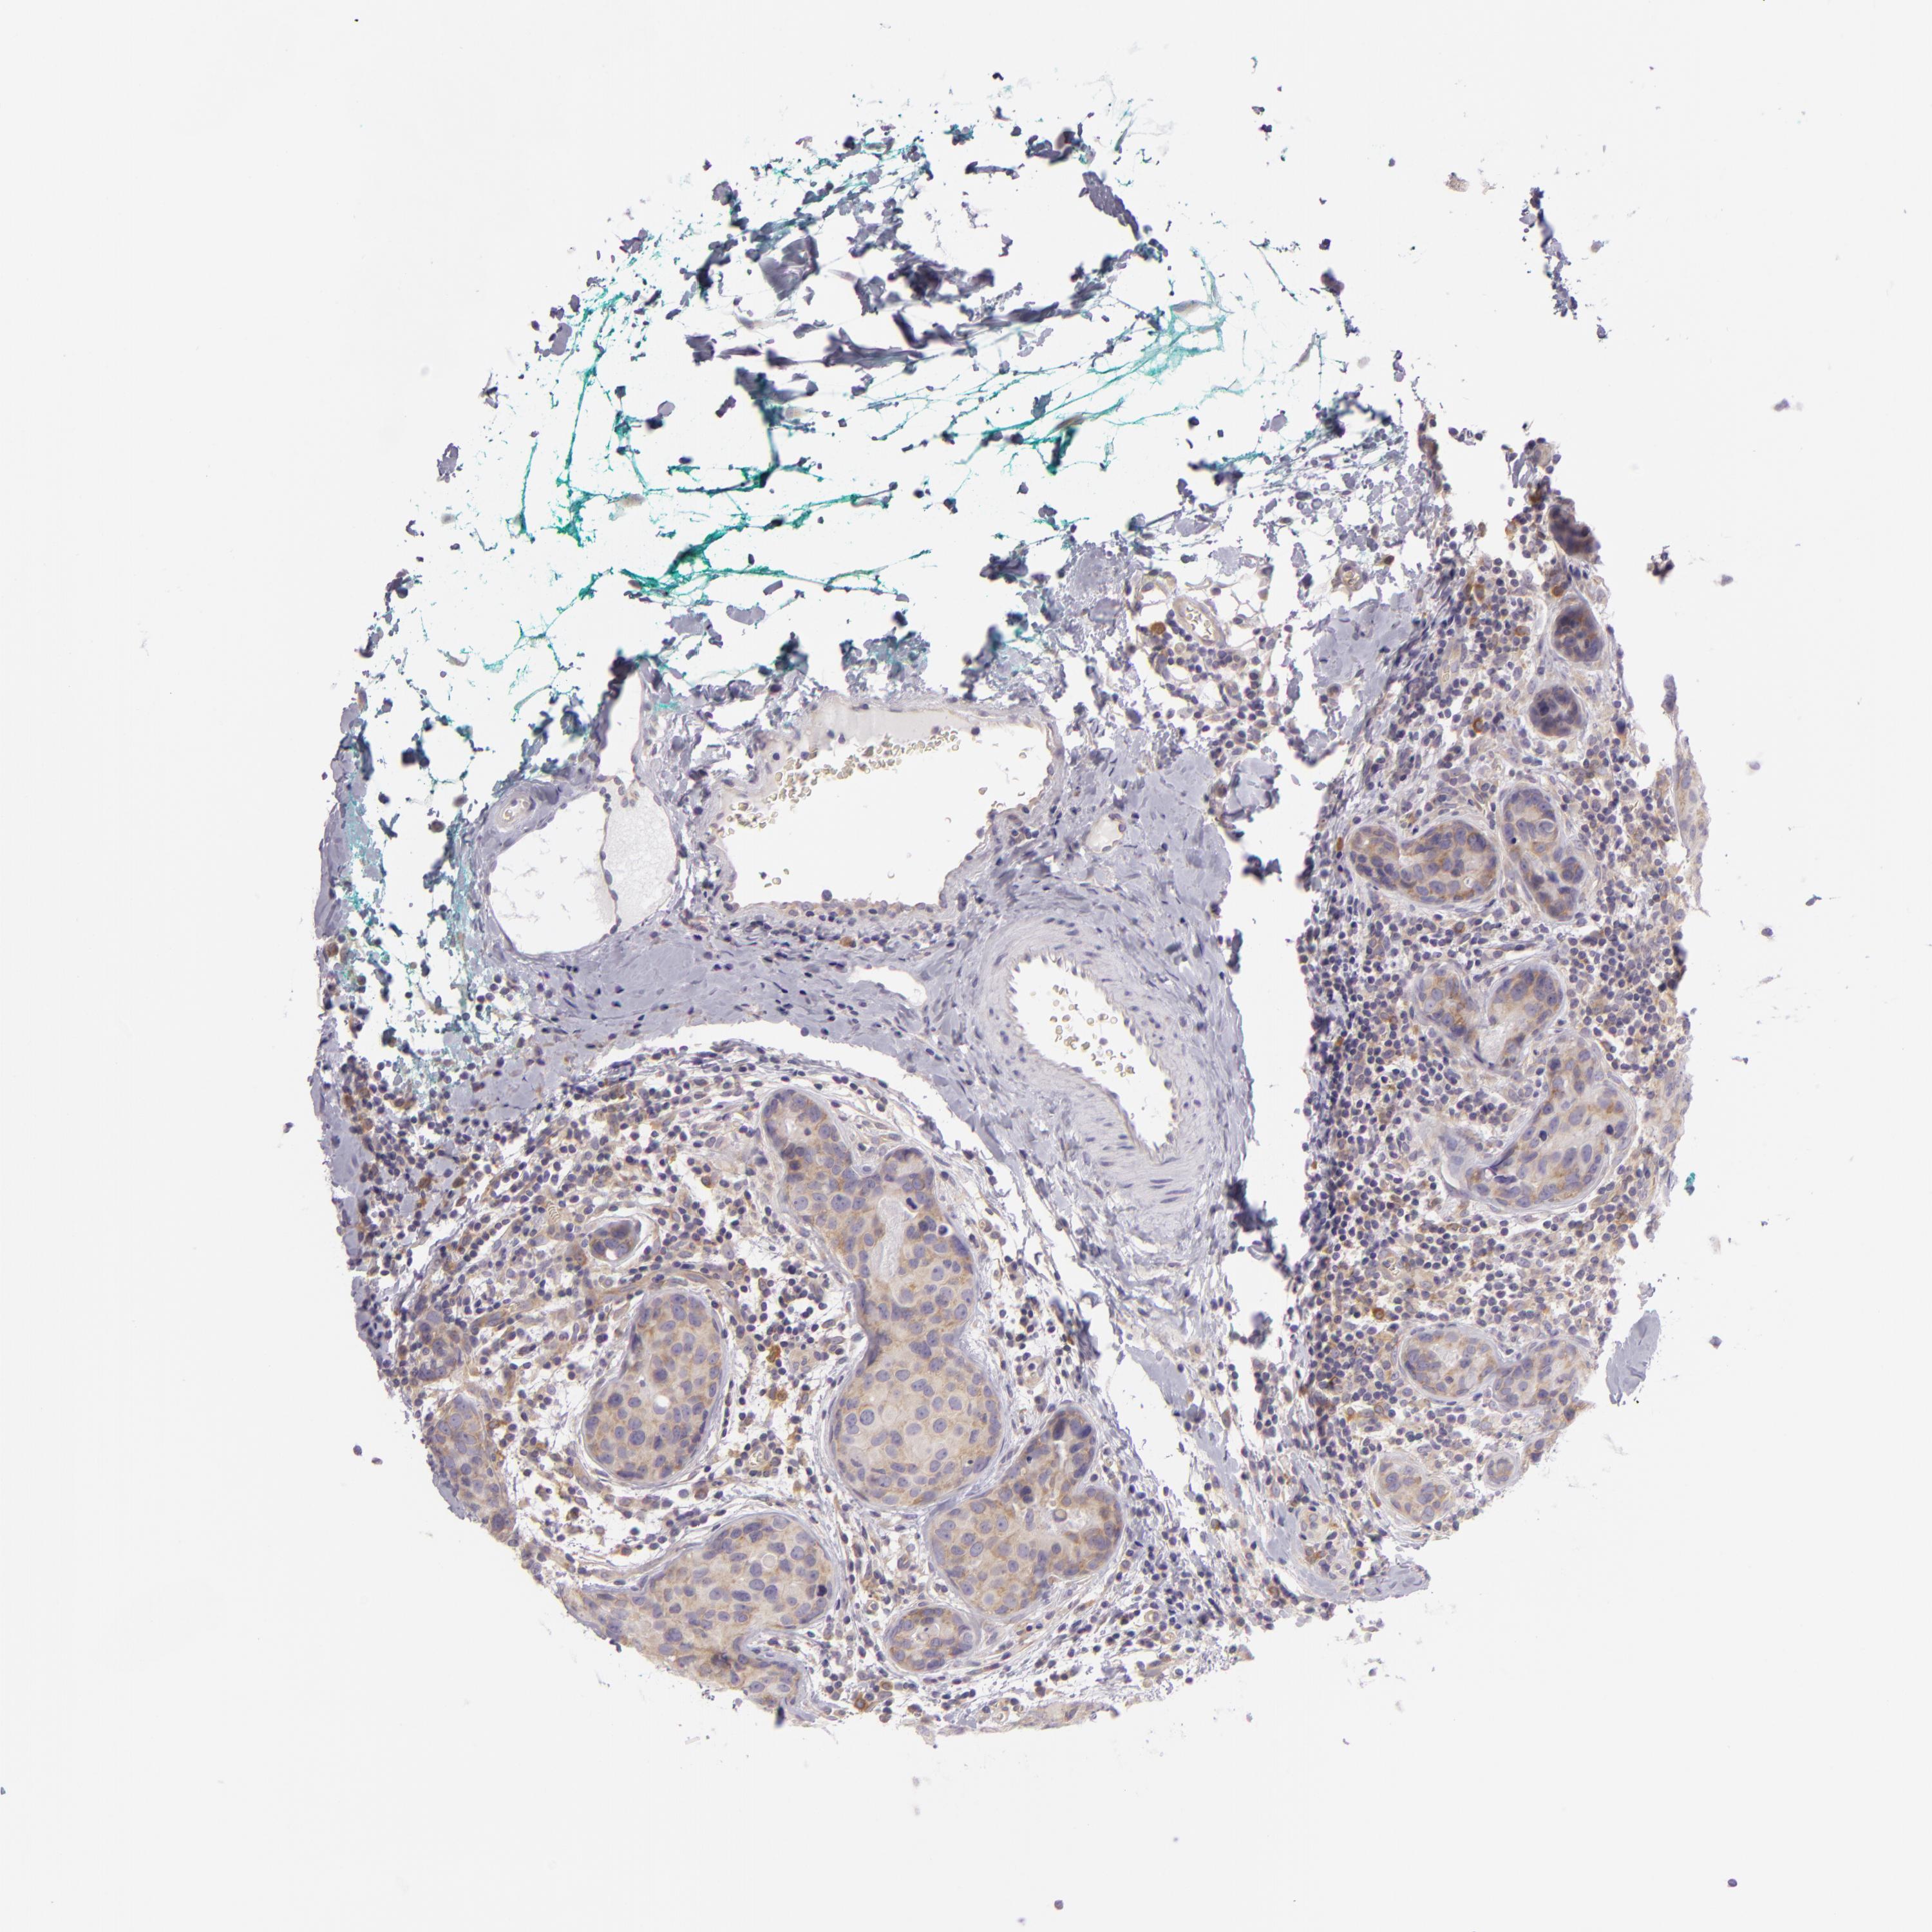

CANCER BREAST CANCER Show tissue menu

BRCA TCGA BRCA VALIDATION PROTEIN EXPRESSION

ANTIBODIES

AND

VALIDATION